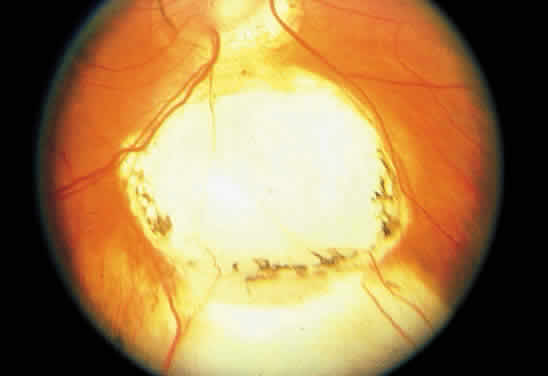

Retinochoroidal colobomas are glistening white or yellow defects with distinct borders that occur inferior or inferonasal to the optic disc (Fig. 12). They may extend up to and involve the optic disc (Fig. 13), or they may be seen as isolated chorioretinal defects. The margins of the coloboma often are pigmented, and the defect is filled with abnormal retinal tissue. Anteriorly, the defect can extend as far as the iris and produce an inferonasal gap (Fig. 14). These anomalies may occur in otherwise normal persons or in association with chromosomal abnormalities or multisystem diseases, such as trisomy 13, the Aicardi syndrome, Goldenhar's syndrome, and the CHARGE association.148,152,153 Occasionally, autosomal dominant or recessive inheritance patterns are found, but often none are evident.152 In families with autosomal dominant inheritance, variable expression of the genetic trait makes genetic counseling difficult.154

Fig. 12. Isolated retinochoroidal coloboma with pigmented borders positioned inferior to the nerve head. The sclera is visible through the thinned, overlying retinal tissue.

Fig. 13. Retinochoroidal coloboma involving the optic disc and inferonasal fundus. The borders of the abnormality are nonpigmented, and the defect appears to be filled with fibroglial tissue.

Embryologically, retinochoroidal colobomas arise from failure of the embryonic fissure to close. Consequently, the inner and outer layers of the optic cup are abnormal in this region. The inner layer (sensory retina) usually is present as a membrane of undifferentiated retina that may have blood vessels going through it (see Figs. 12 and 13). The outer layer (RPE) is absent, and since the choroid is dependent on the RPE for its development, it also is lacking.